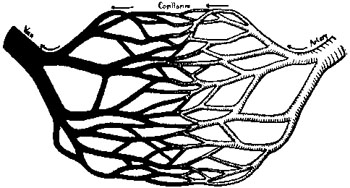

114 Diagram of Artery, Capillaries, and Vein